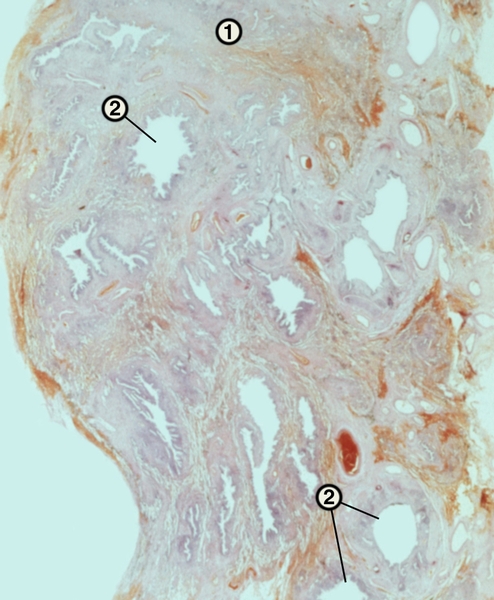

Микроскопический взгляд на мишитарный туберкулез легкого: фотодокументация